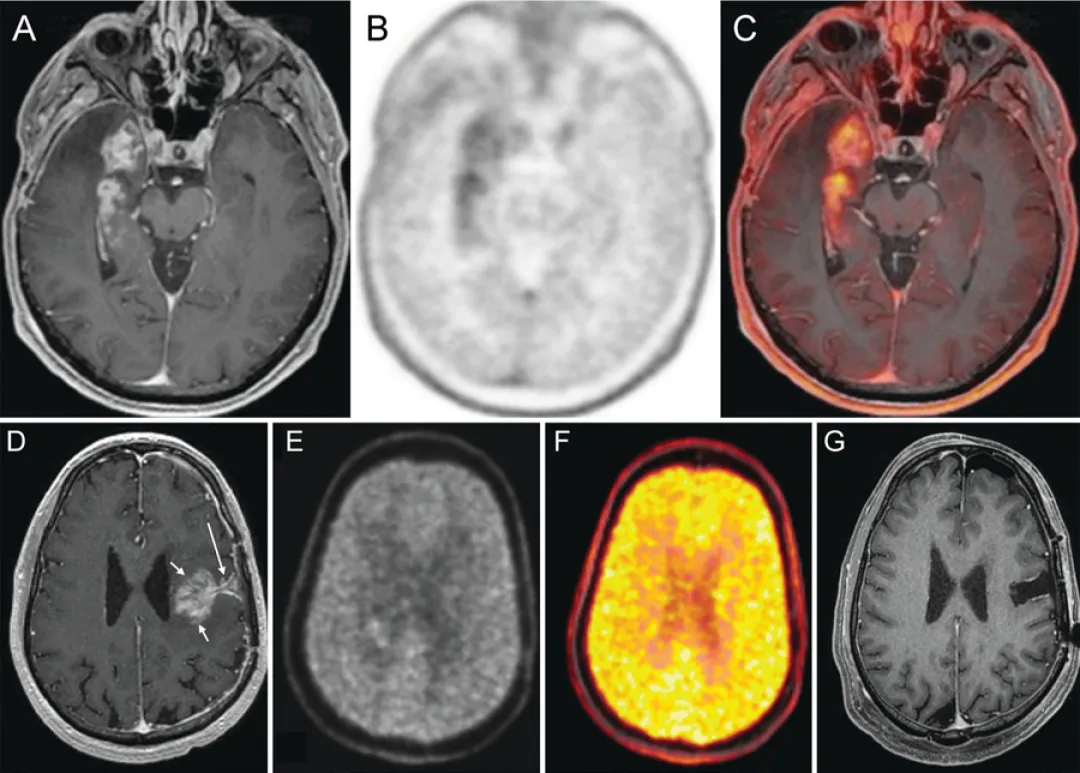

正电子发射断层扫描(FET)

正电子发射断层扫描已成为另一种重要的影像学手段,其通过使用放射性标记的氨基酸示踪剂(如O-(2-[18F]氟乙基)-L-酪氨酸、3,4-二羟基-6-18F-氟-L-苯丙氨酸或18F-氟代脱氧葡萄糖)来识别代谢活跃的肿瘤区域。该技术基于肿瘤细胞糖酵解过程中代谢活性增强及氨基酸摄取增加的特性。由于脑部PET扫描存在本底活性低的固有局限性,FET可能优于FDG。最新研究不仅支持FET的高敏感性与特异性,还证实其能准确指导治疗决策,FDOPA在诊断性活检中同样具有价值。

图5. PET在复发判断中的应用案例

A-C:右颞叶GBM放疗后6个月

A:轴位T1增强MRI显示右内侧颞叶占位性强化

B:轴位FDOPA PET显示右颞区代谢摄取增高

C:轴位FDOPA PET-MR融合图像精确显示代谢活性定位于右内侧颞叶占位

D-G:左额叶复发性GBM再程放疗联合免疫治疗后2个月

D:轴位T1增强MRI显示手术切缘深部(长箭头)类肿块强化灶(短箭头),基于此影像行再次切除

E:轴位FDOPA图像显示强化灶内无摄取增高

F:轴位FDOPA伪彩图显示强化灶内无摄取增高

G:再次切除术后1月轴位T1增强MRI显示无残留强化